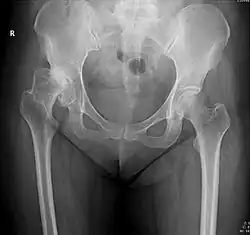

Projectional radiography ("X-ray") is the first imaging technique of choice in hip pain, not only in older people with suspected osteoarthritis but also in young people without any such suspicion. In this case plain radiography allows categorization as normal hip or dysplastic hip, or with impingement signs, pincer, cam, or a combination of both.[1]

X-Ray

Projectional radiography ("X-ray") is currently useful not only in older people in whom osteoarthritis of the hip is suspected but also in younger people without osteoarthritis, who are being evaluated for femoroacetabular impingement (FAI) or hip dysplasia.[1]

Plain radiography allows us to categorize the hip as normal or dysplastic or with impingement signs (pincer, cam, or a combination of both). Besides these, pathologic processes like osteoarthritis, inflammatory diseases, infection, or tumors can also be identified (Figure 1).[1]

X-ray of the hips of a 40-year-old female, with dysplasia of her right hip.